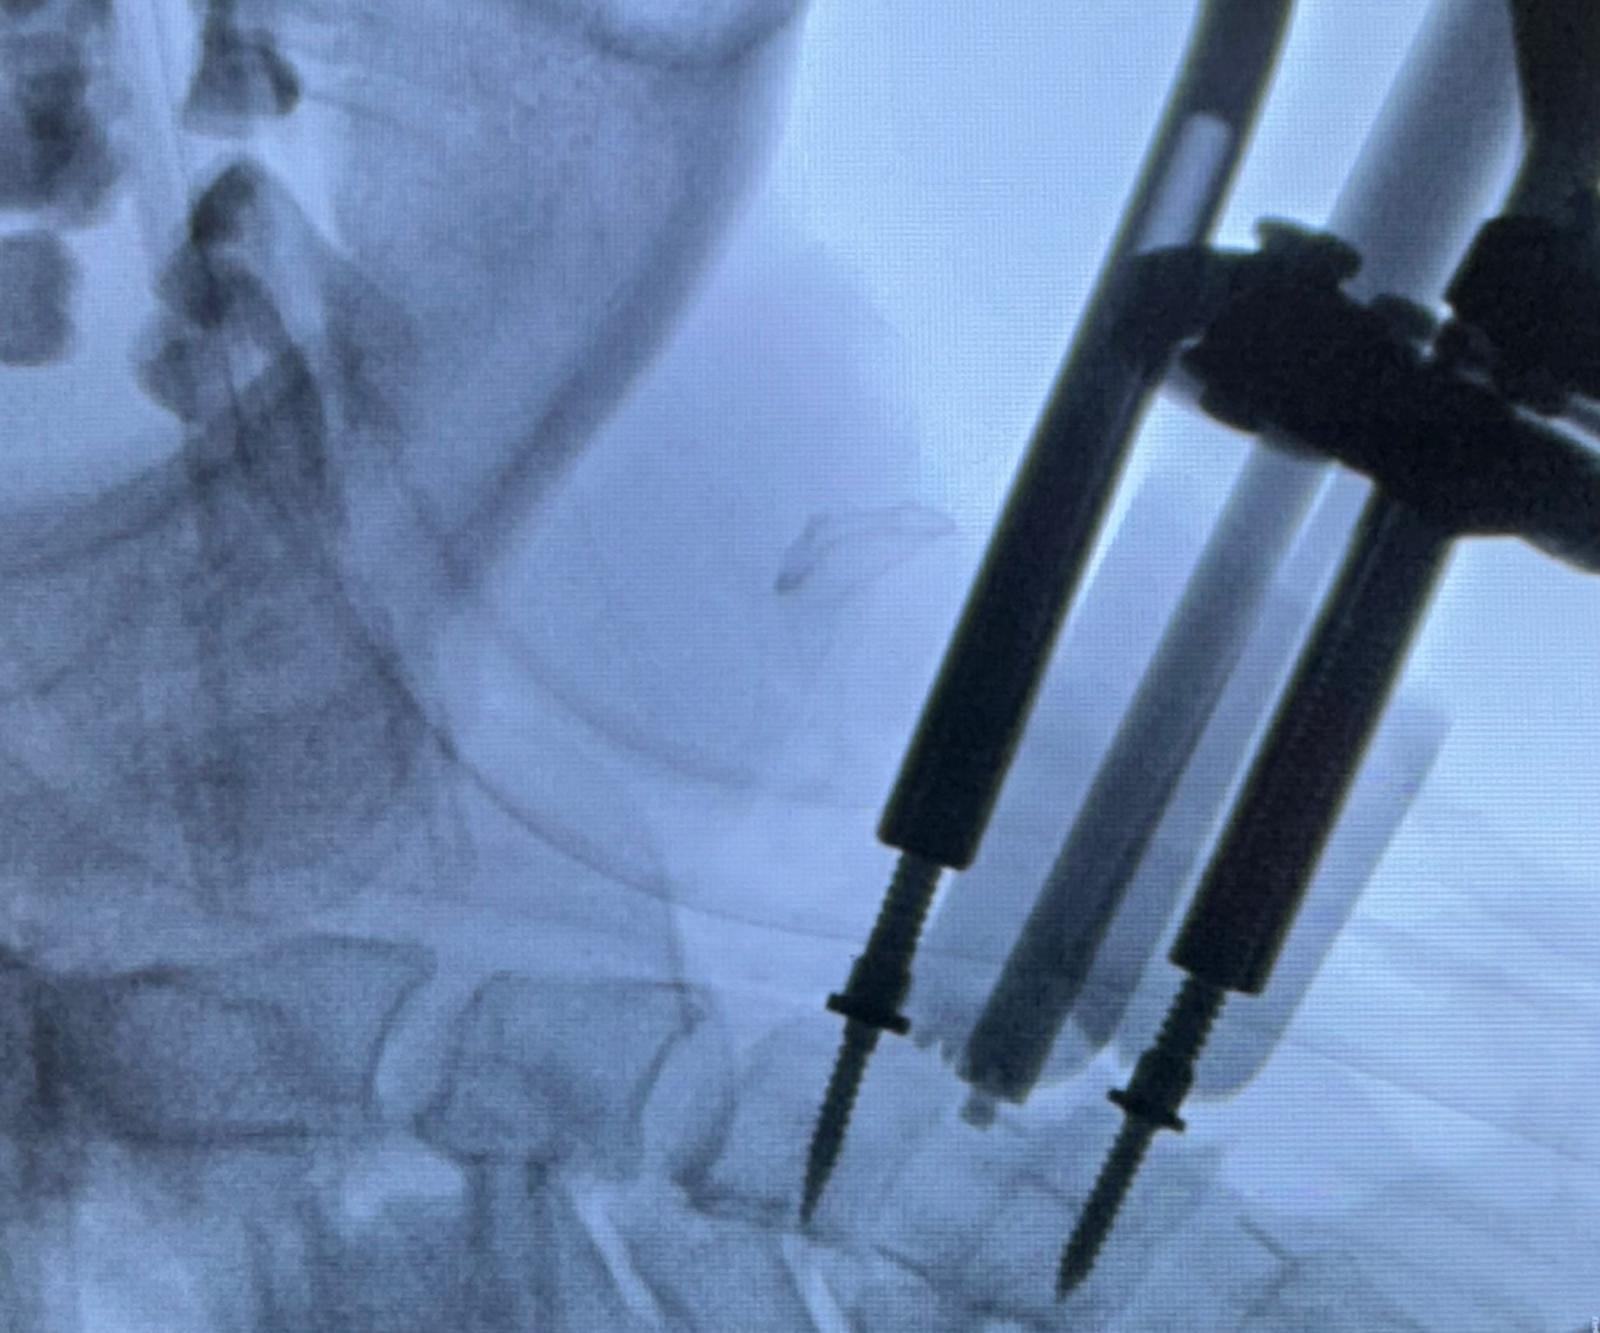

Termolezja, znana również jako ablacja termiczna, to procedura medyczna, która ma na celu złagodzenie przewlekłego bólu, zwłaszcza w okolicy kręgosłupa lędźwiowego. Zabieg polega na zastosowaniu prądu o wysokiej częstotliwości (300–500 kHz), który generuje ciepło w tkankach, prowadząc do zniszczenia nerwów odpowiedzialnych za przewodzenie sygnałów bólowych.

Jest to procedura małoinwazyjna – nie wymaga nacięć chirurgicznych ani hospitalizacji, a pacjent może wrócić do codziennych zajęć już po krótkiej rekonwalescencji. Termolezja stosowana jest przede wszystkim u osób cierpiących na przewlekłe bóle kręgosłupa, neuralgie czy bóle korzeniowe, które nie reagują na leczenie farmakologiczne czy rehabilitację.

Zabieg jest bezpieczny, dobrze tolerowany i pozwala ograniczyć stosowanie silnych leków przeciwbólowych.